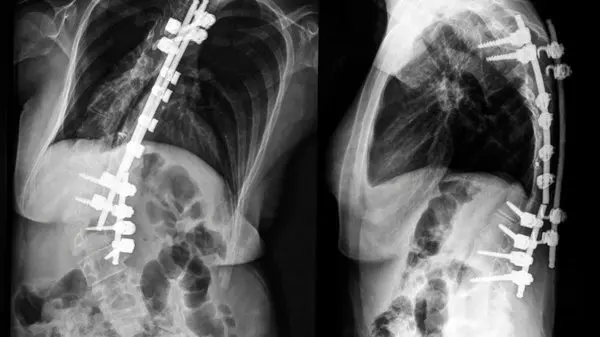

تشخیص این بیماری معمولاً با معاینه فیزیکی آغاز میشود. پزشک ممکن است از بیمار بخواهد که به جلو خم شود تا انحراف ستون فقرات را بررسی کند. بعد از آن، معمولاً از رادیوگرافی (X-ray) برای ارزیابی دقیقتر و اندازهگیری میزان انحراف استفاده میشود. تصاویر رادیوگرافی به پزشک کمک میکند تا تصمیم بگیرد که درمان لازم است یا خیر.

جراحی:

اگر انحراف شدید باشد (معمولاً بالای ۴۰-۵۰ درجه)، و به درد یا مشکلات تنفسی منجر شود، ممکن است جراحی لازم باشد. در این جراحی، پزشک معمولاً از روشهایی مانند فیوژن مهرهها (اتصال دو یا چند مهره به هم) یا نصب پیچ و پلاک برای اصلاح انحراف استفاده میکند.